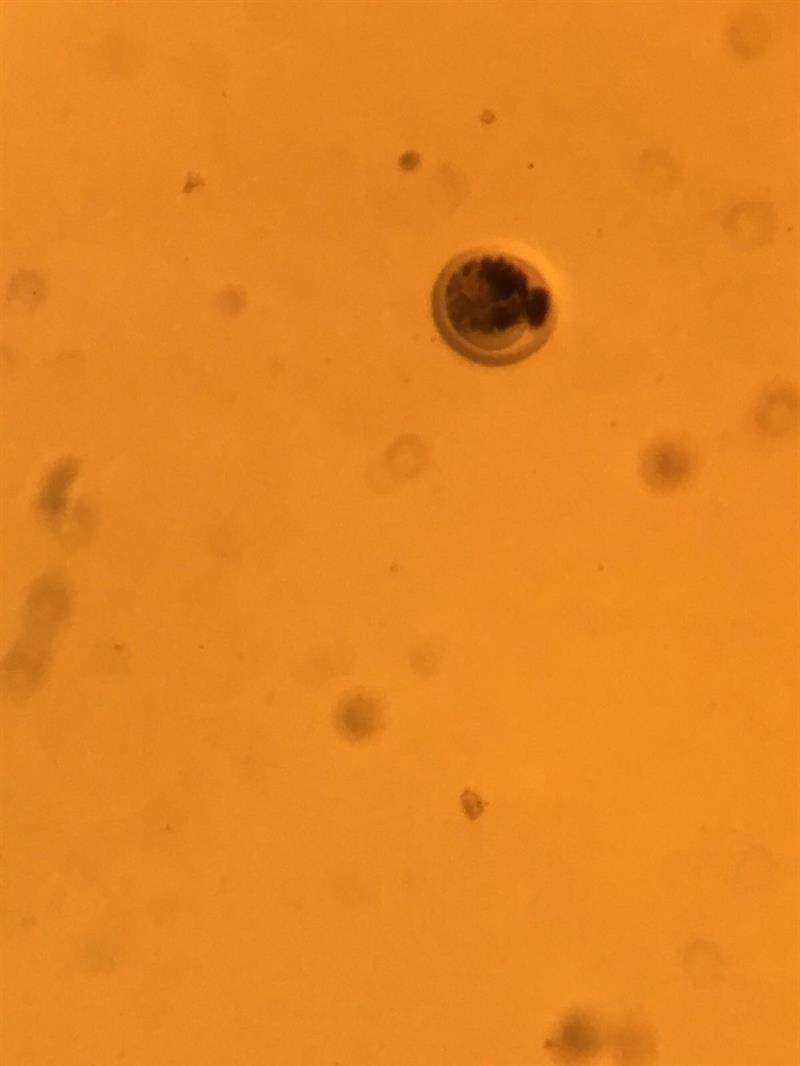

Konya Selçuk Üniversitesi Veteriner Fakültesi Sığırlarda Embriyo Üretimi ve Transferi Kursu Düzenlenmiştir.

​Hayvancılık Genel Müdürlüğü ve Selçuk Üniversitesi Sürekli Eğitim Merkezi (SÜSEM) işbirliği ile 3 hafta süren Veteriner Hekimlere yönelik Sığırlarda Embriyo Üretimi ve Transferi Kursu; Selçuk Üniversitesi Veteriner Fakültesi Suni Tohumlama Anabilim Dalı Öğretim Üyeleri Sayın Prof. Dr. Mehmet Bozkurt ATAMAN, Prof. Dr. Abdullah KAYA ve Prof. Dr. Mustafa Numan BUCAK tarafından 03-21 Temmuz 2017 tarihleri arasında düzenlenmiştir. 10 kişilik grup teorik ve pratik uygulamaları kapsayan eğitimini başarı ile tamamlamıştır. Kursun ilk haftası Genel Müdürlüğümüzce Veteriner Hekim Ali İhsan AKIN, Veteriner Hekim Adem ONUR ve Veteriner Hekim Mustafa ONUR tarafından denetlenmiştir. Kursun son haftasında Veteriner Hekim Dr. Senem HACIÖMEROĞLU ve Veteriner Hekim Tahsin DİLİK tarafından denetlenmiş katılımcılara Embriyo Uygulamaları ve Mevzuatı hakkında bilgi verilmiştir. Talep olması durumunda bu eğitimlere devam edilecektir.